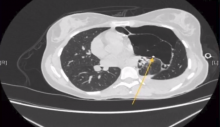

This video demonstrates a video-assisted thoracoscopic resection of a congenital lobar emphysema in a young woman with spontaneous pneumothorax. Congenital lobar emphysema occurs when there is a developmental ball-valve obstruction in the bronchial tree. This is usually related to bronchial malformation and most commonly affects the left upper lobe.

Small osseous formations were observed in the resected lobe. Pulmonary osseous metaplasia (OM) is a poorly understood phenomenon related to chronic inflammation and possibly related to fibroblast transformation triggered by TGF-β. Most cases of pulmonary OM are reported in conjunction with usual interstitial pneumonia, but it has also been described to a lesser extent in other lung conditions. A diffuse (dendriform) bilateral form of the disease has also been described.